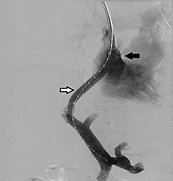

- In most cases, there is a gastrorenal or gastrocaval shunt. In this situation under fluoroscopic guidance, a balloon catheter is inserted into the outlet of the gastrorenal or gastrocaval shunt through a sheath placed in the right femoral vein.

- Immediately afterward, venography is performed with an injection of 10–15 mL contrast medium via the inflated balloon catheter, and GV are slowly, intermittently, and completely filled with a sclerosant.